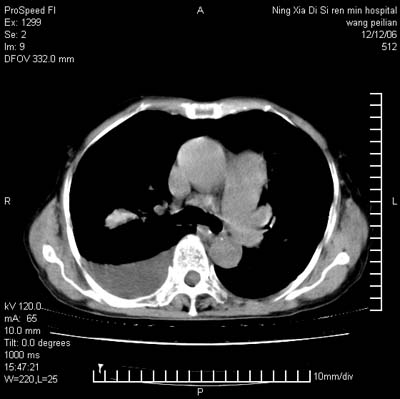

标题: CT5609:胸部:女77 病史不详

两肺可见多个大小不等的结节,左侧有胸水,纵隔淋巴结增大,考虑是细支气管肺泡癌

两肺尖纤维索状影,两下肺结节块状影,且有钙化灶,右胸腔积液。考虑肺结核并胸膜炎。

两肺尖纤维索状影,两下肺结节块状影,且有钙化灶,右胸腔积液。考虑肺结核并胸膜炎肺间质纤维化

考虑:1、慢性支气管炎合并全小叶型肺气肿、间质纤维化;

2、双肺结核;

3、右侧胸膜炎(积液)。

1、双肺继发型肺结核(以纤维、增殖灶为主);

2、右侧胸腔积液;

3、其余符合老年肺改变。

双肺见多个结节状及条索状影,双侧胸腔积液,右侧叶间积液,考虑结核性胸膜炎